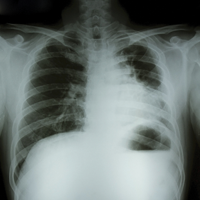

БА — широко распространенное хроническое заболевание, при котором отмечают периоды обратимой обструкции дыхательных путей. Во время таких эпизодов свободному потоку воздуха препятствует воспаление и состояние повышенной реактивности (сокращение гладких мышц) дыхательных путей в ответ на воздействие какого-либо раздражителя (физическая активность, инфекционные и неинфекционные агенты, аллергены, химические вещества). К симптомам приступа БА относят одышку, кашель, затруднение дыхания и ощущение стеснения в груди.